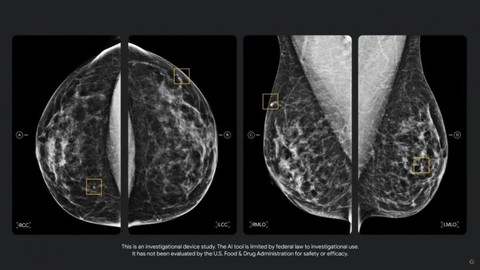

通过跟西北医学的合作,谷歌将研究更好的乳房X光检查技术从而改善乳腺癌筛查过程。借助 AI 来扫描 X 光图像,并通过邮件发送给医生来进一步分析。患者可以通过使用AI扫描乳房X光片在医生同意接受的情况下将其通过电邮发送给医生以获得进一步的分析。与此同时,AI 健康应用也能够造福许多普通人。